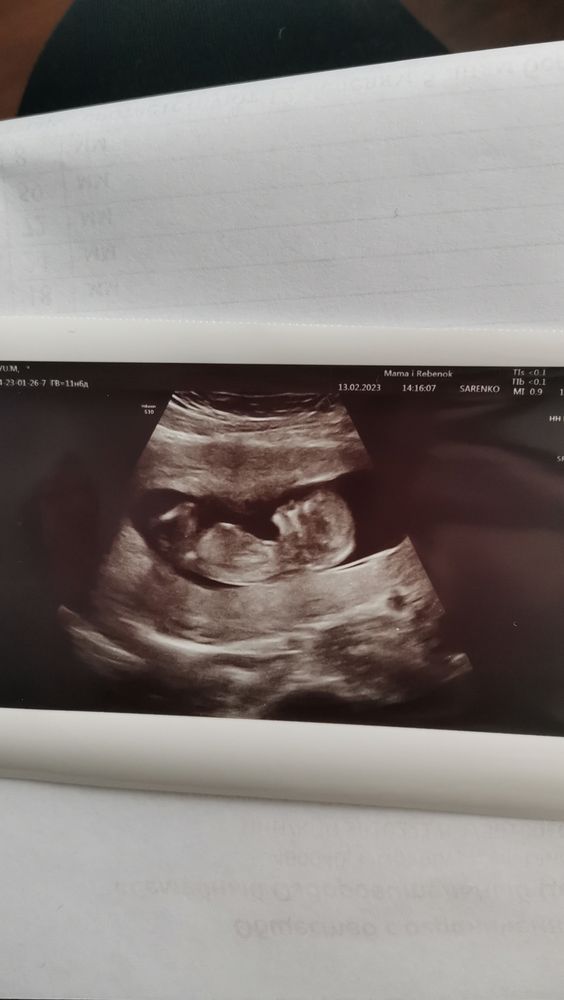

Первый скрининг 12 недель

В профиль - серьёзный человек😁